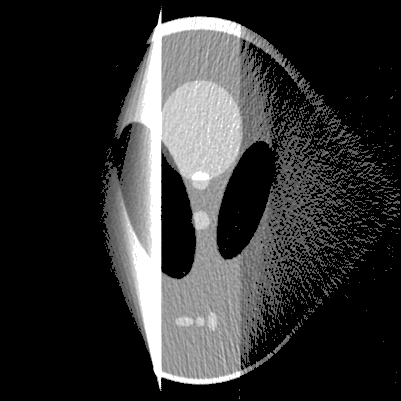

The proposed method was performed for various computer-simulated data, including perfect, noisy, non-truncated and truncated data. Figure 2 displays the reconstructed images from perfect data, while figure 3 displays the reconstruction from noised data for and . The images in top row are reconstructed from non-truncated projection data, while these in the bottom row are reconstructed from the truncated data such that any measurement corresponding to a line not passing through the rectangular box in figure 1(a) was discarded.

From figures 2 and 3, we can see that the presented algorithms can carry out the reconstruction of SPECT efficiently. As our expectation, the distortions in the reconstructions raise with the increase of the attenuation coefficient . The profiles of the reconstructions in figure 2 at are displayed in figure 4. Similar to [1], we have the same observation that the noise in the reconstructions appears strongly spatial variant, for which the reason is the weight variant in (3)(see [1] for details).